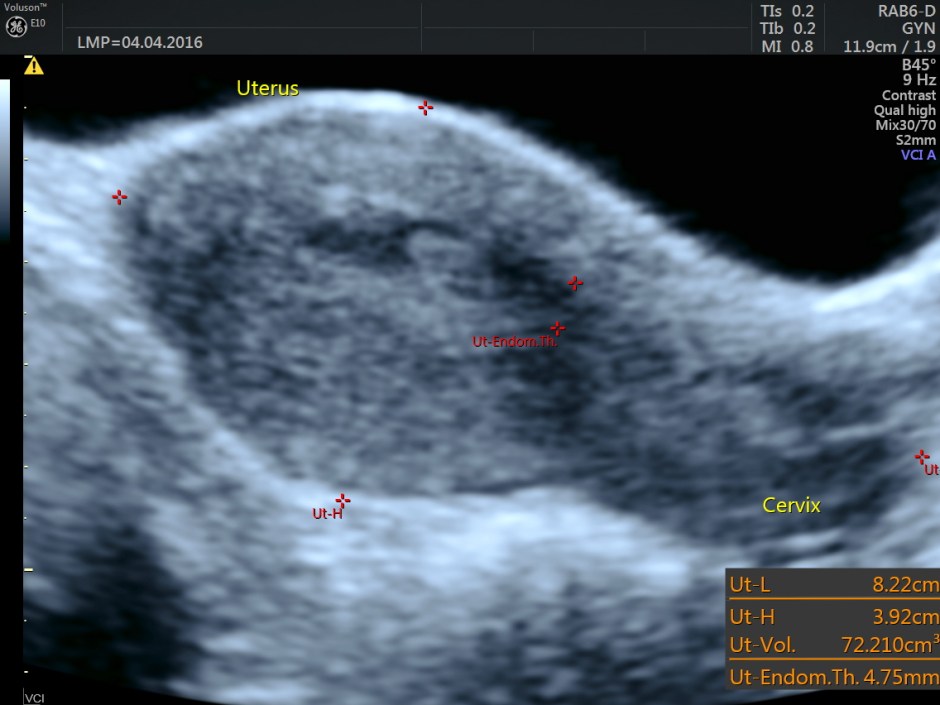

The uterus in 2 D is shown below.

Trans abdominal view

Transvaginal view

Endometrium shows ? polypoid appearance; Irregular hypoechoic myometrial texture with some serpiginous appearance is seen.